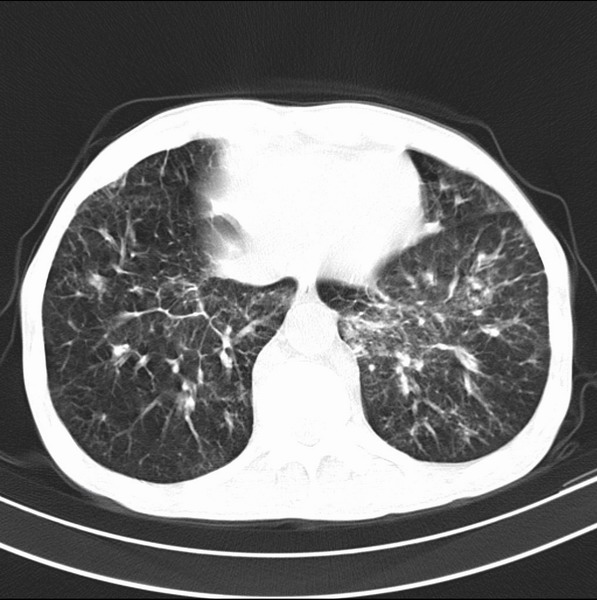

标题: CT19600:能否诊断为转移?

女、55

3年前盲肠癌、一年半前诊断膀胱癌,现在呼吸困难,临床考虑为肺转移

请问胸部ct如何诊断?能否排除淋巴管炎,纵隔窗没有问题。

考虑间质性病变,癌性淋巴管炎可能.

转移,癌性淋巴管炎。

建议抗炎后复查,不除外癌性淋巴管炎。

考虑间质性病变,癌性淋巴管炎可能.支持!

支持考虑间质性病变,癌性淋巴管炎可能.